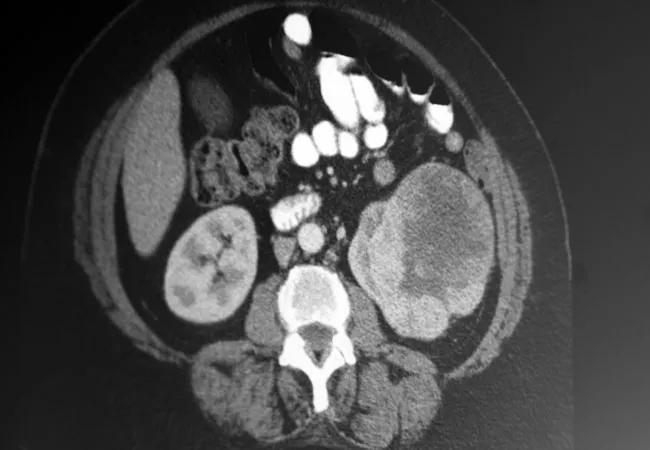

RCC_650x450